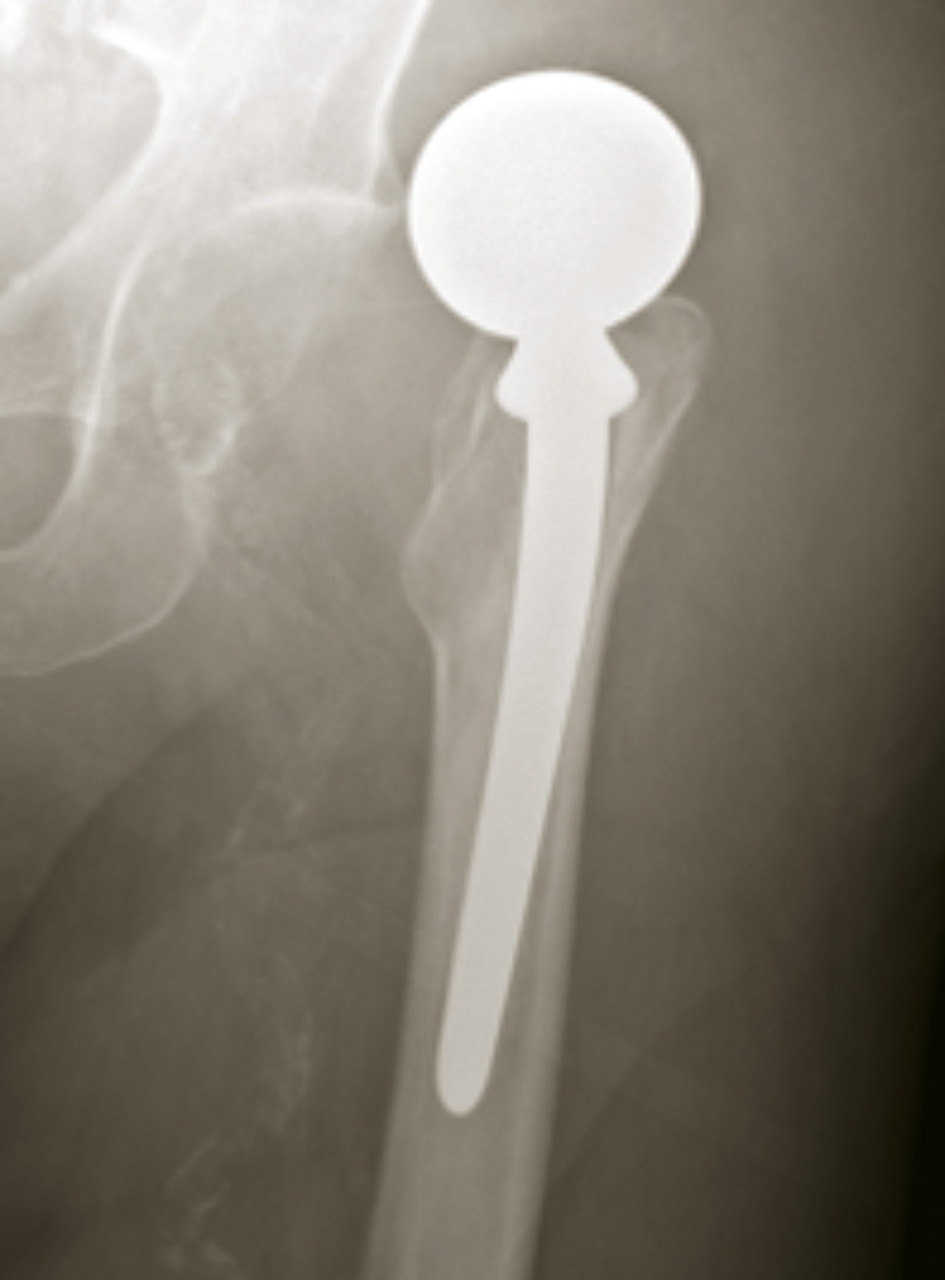

En cas de fracture cervicale vraie Garden III ou IV, le risque de nécrose est important, et il est préférable de s’orienter vers un remplacement prothétique (fig. 14). Il peut s’agir d’une prothèse céphalique où la prothèse remplace uniquement la tête fémorale. Il peut s’agir d’une prothèse intermédiaire qui remplace la tête fémorale mais avec un système de double glissement qui améliore la stabilité de l’implant et diminue les risques d’usure de l’acetabulum. Il peut s’agir d’une prothèse totale de hanche. L’utilisation ou non du ciment pour la fixation de la prothèse ne fait pas consensus dans la littérature, chaque méthode ayant ses avantages et ses inconvénients. Toutefois, chez les patients jeunes, en général de moins de 50 ans, malgré les risques de nécrose, l'ostéosynthèse est conseillée, même dans les fractures Garden III et IV.

L’arthroplastie est indiquée dans les fractures cervicales vraies Garden III et IV chez les patients âgés.